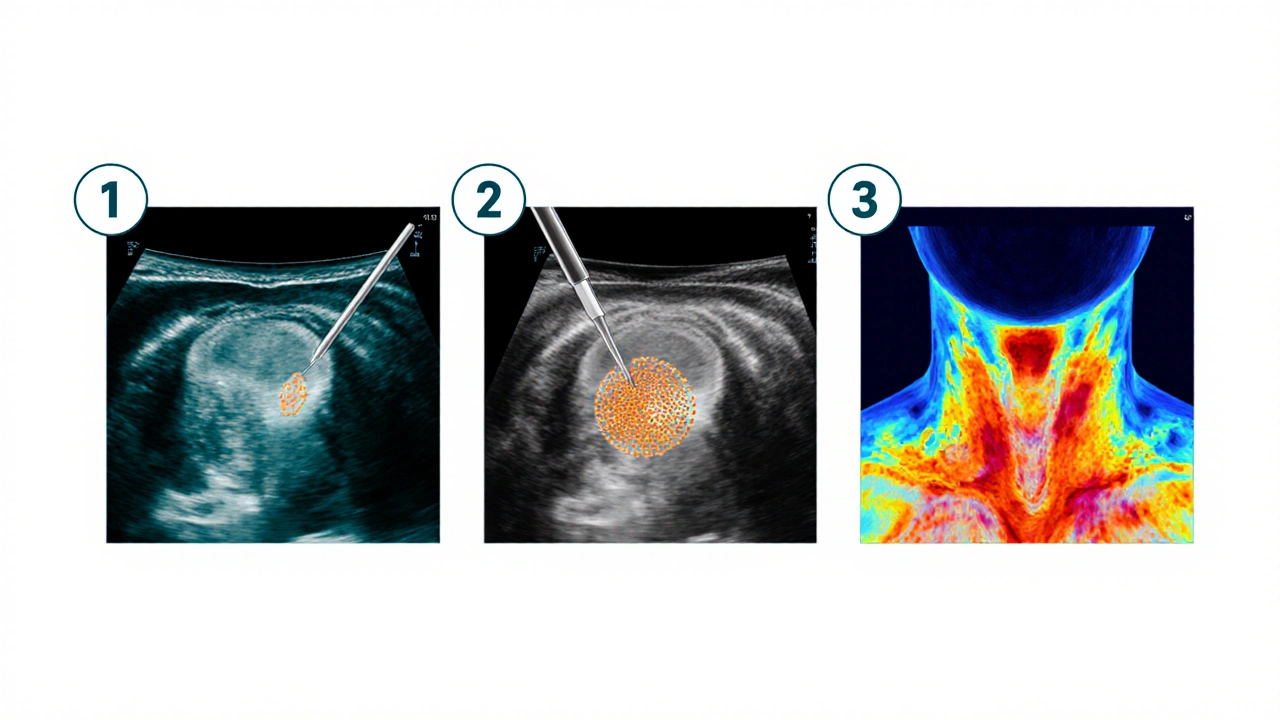

1. Klinické vyšetření a ultrazvuk

Prvním krokem je fyzické vyšetření krku a ultrazvukové zobrazování. Ultrazvuk odhalí tvar, velikost a strukturu uzlu, a pomůže odlišit solidní (pevné) změny od cystických (naplněných tekutinou).

2. Fine-needle aspiration (FNA) - jemná jehlová aspirace

Pod ultrazvukovým vedením se do podezřeleho uzlu zavede tenká jehla a odebere se vzorek buněk. Cytologický rozbor (Papova test) určuje, zda jsou buňky benigní, maligní nebo borderline.

3. Skintigrafie štítné žlázy

Pacient dostane malé množství radioaktivního jódu (I‑131) nebo technetu‑99m. Sken ukáže, zda jsou buňky aktivní (tzv. „hotý“ uzly) nebo nečinné („cold“ uzly), přičemž „cold“ uzly mají vyšší pravděpodobnost malignity.